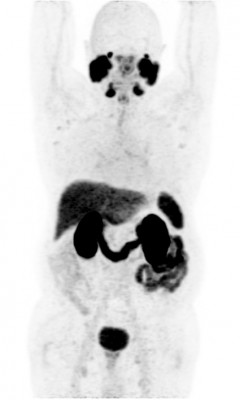

Позитронная эмиссионная томография (ПЭТ/КТ) всего тела с 68Ga-PSMA

Рак предстательной железы — оценка распространенности опухолевого процесса, оценка эффективности противоопухолевого лечения, диагностика рецидива (при уровне ПСА от 0,2 нг/мл).

| Метастазы в кости скелета при раке предстательной железы | Нормальное распределение РФП в организме |